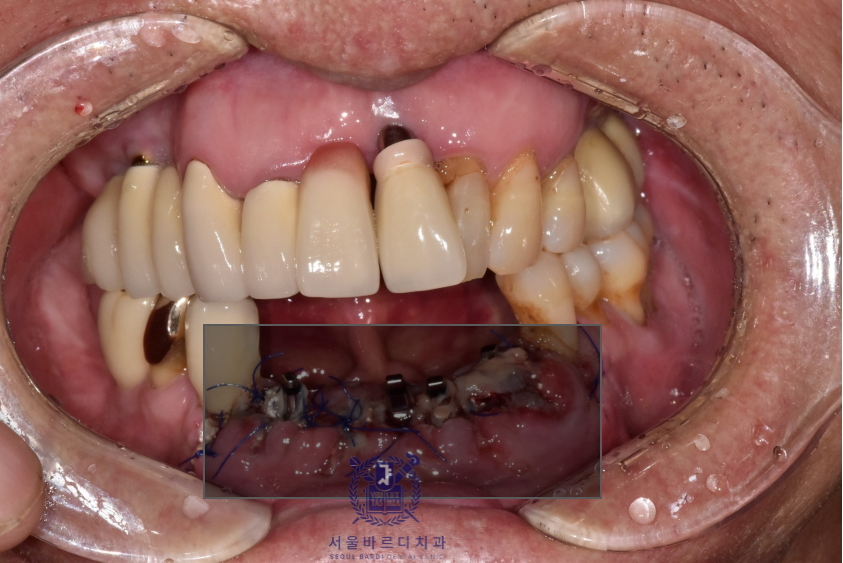

왼쪽 위 역시 가장 이상적인 위치에 성공적으로 임플란트를 식립하였습니다.

다행히 수술 후 지혈도 잘 되시고 회복하는 과정에도

환자분이 지시에 잘 따라주셔서 잇몸도 예쁘게 아물었습니다.

아래 앞니는 6개의 치아를 안정적으로 유지할 수 있는

견고한 4개의 뿌리를 식립하였고

왼쪽 위는 큰어금니 다음으로 중요한 역할을 수행할 작은

어금니에 맞는 사이즈로 식립하였습니다.

성공적으로 보철까지 잘 마무리 해드렸습니다.

앞으로 새로 할 보철은 깨끗한 색이였으면 한다고 하셔서

앞니는 조금 밝은 색으로 진행하게 되었습니다.

아래 컬러에 맞춰 기존에 있는 보철들도 추후 차례대로 교체하기로하셨습니다.

앞니는 기능적이면도 있지만 심미적인 측면이 매우 중요하기 때문에

최대한 환자분에게 적합한 형태로

환자분의 의견을 적극 반영하여 제작하고 있습니다.

이전의 브릿지 보철은 공간을 꽉 채우는 느낌으로 제작되어

이가 너무 길어보이는 느낌이 있어

이번에는 볼륨을 통해 치아가 길어보이지 않게 제작했습니다.

실제로 치아가 보이는 부분은 이 앞의 보철과는 다르게

짧게 표현되어 환자분이 아주 만족스러워하셨습니다.

더불어 뭉툭하고 긴 치아표면으로 인해 양치가 어려웠지만

이번 디자인은 치아가 볼륨을 통해 나눠져 있어

양치하시기도 훨씬 수월하시다고 합니다.